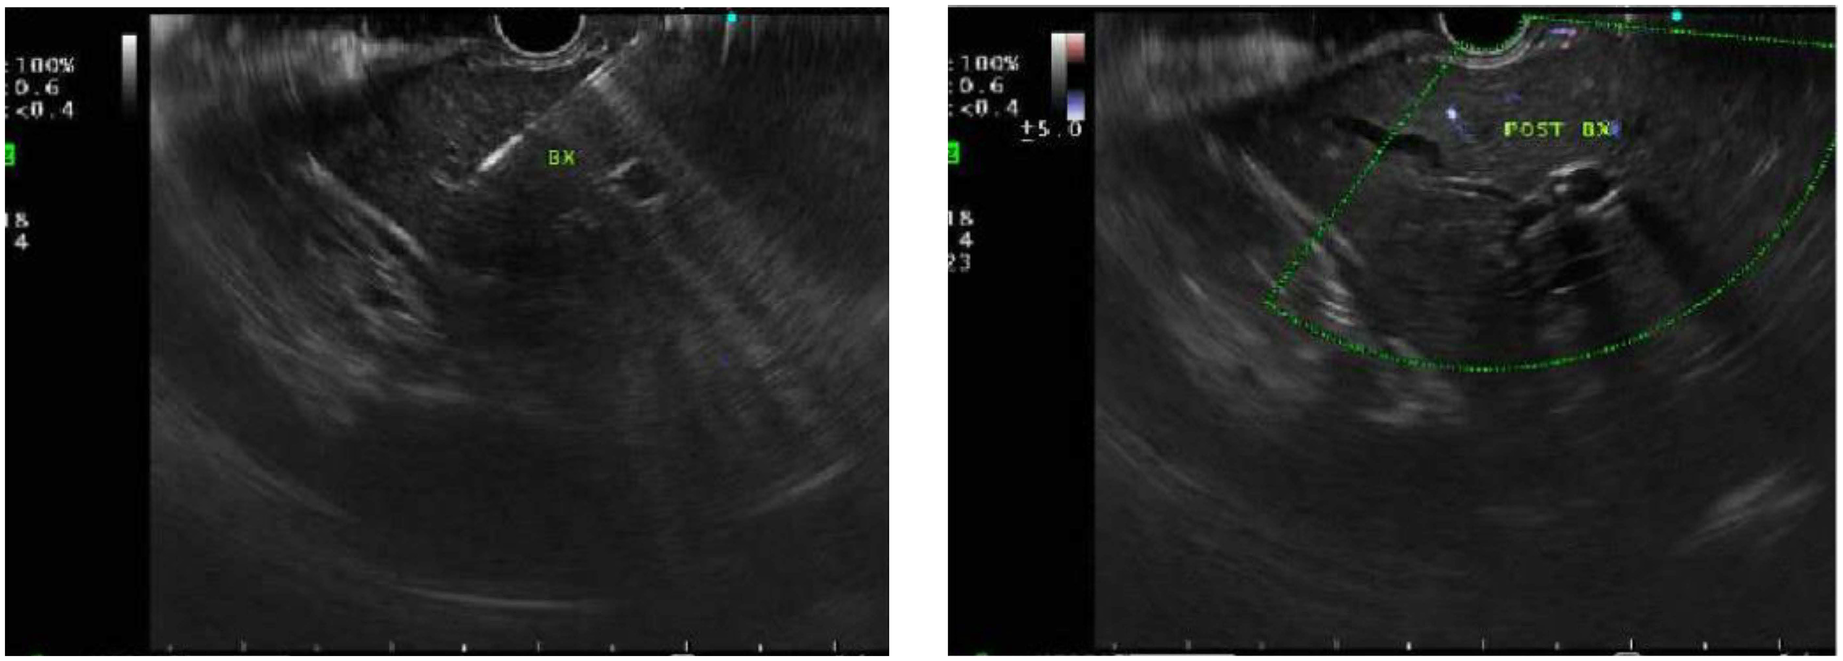

A total of 148 (50.3%) EUS procedures were performed for biliary/hepatic indications. Among them, 100 (67.6%) were performed for suspected choledocholithiasis in whom ultrasound sonography (USG) or Magnetic resonance cholangiopancreatography (MRCP) were inconclusive. Performing an initial EUS, averted a total of 10 (10%) ERCPs (Figure 1).

Figure 1. Endoscopic ultrasound (EUS) demonstrating absence of choledocholithiasis, averting endoscopic retrograde cholangiopancreatography (ERCP).